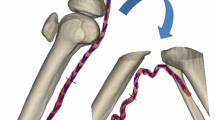

MacTaggart JN, Phillips NY, Lomneth CS et al (2014) Three-dimensional bending, torsion and axial compression of the femoropopliteal artery during limb flexion. J Biomech 47:2249–2256. https://doi.org/10.1016/j.jbiomech.2014.04.053

Poulson W, Kamenskiy A, Seas A et al (2018) Limb flexion-induced axial compression and bending in human femoropopliteal artery segments. J Vasc Surg 67:607–613. https://doi.org/10.1016/j.jvs.2017.01.071